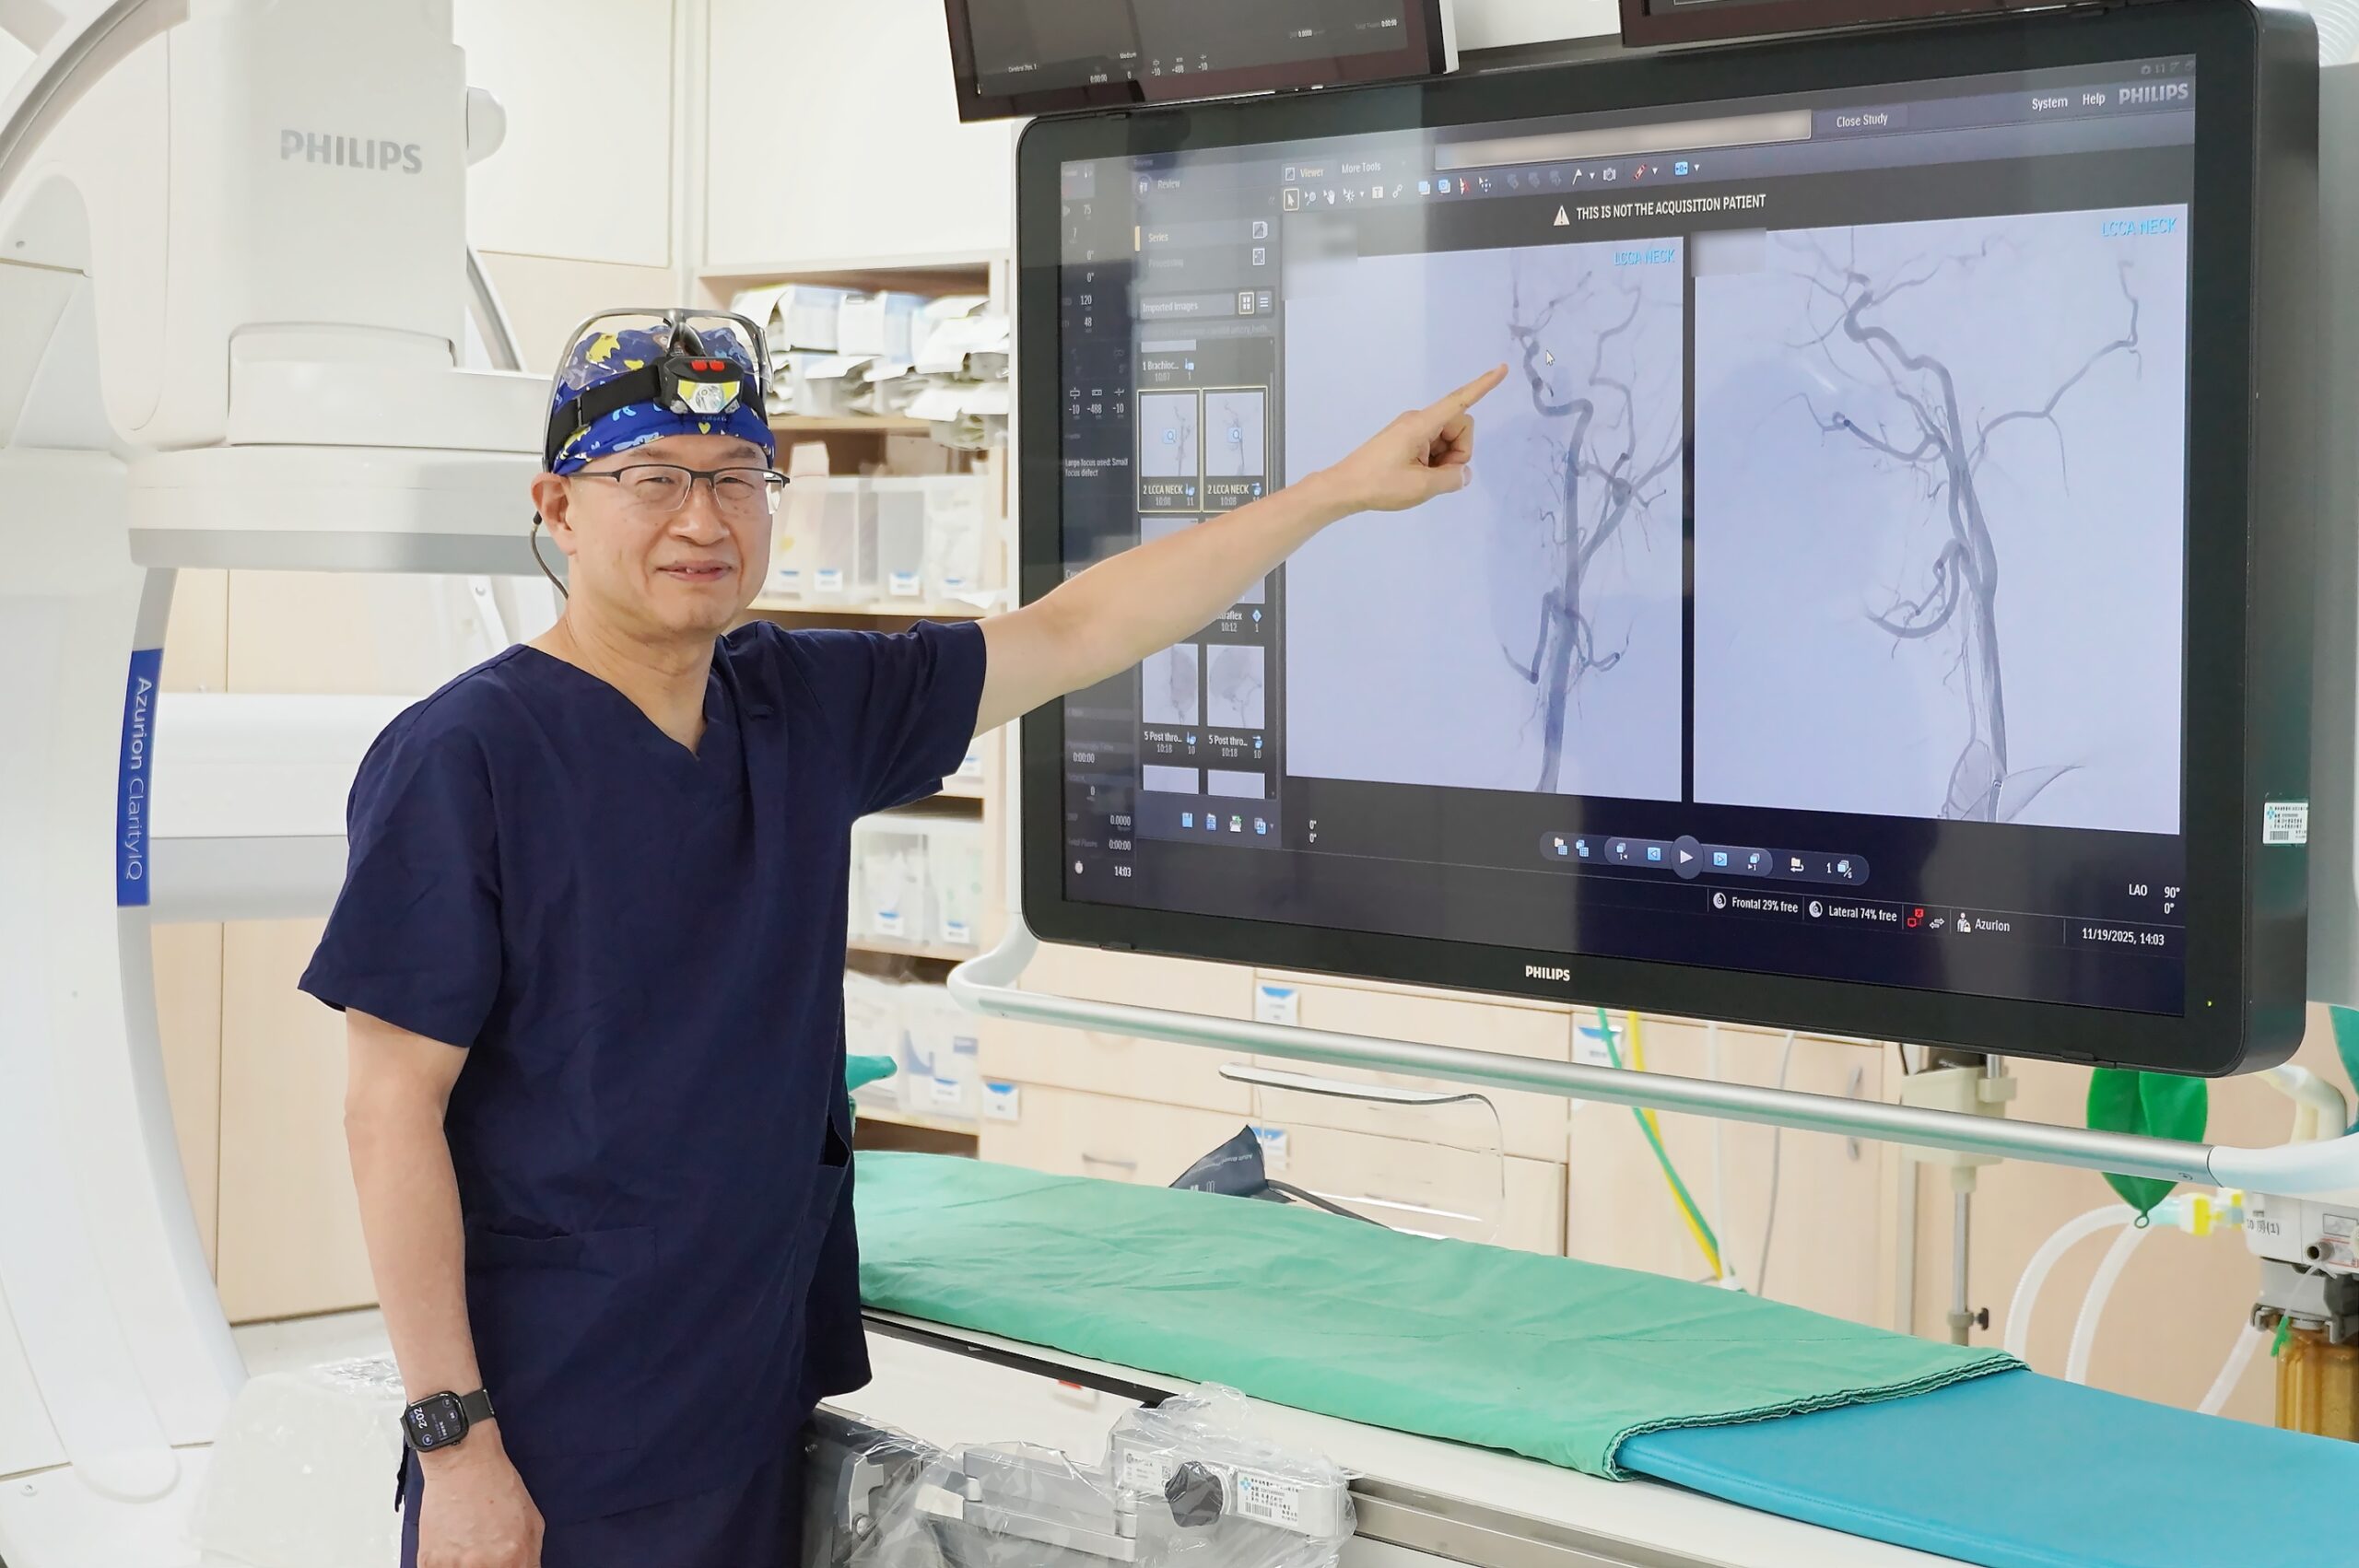

聯新國際醫院表示,該名學生被送往該院急診,影像檢查結果出爐後,神經內科醫師李振華迅速判讀,確定為左側中大腦動脈栓塞造成缺血性腦中風。在與家屬充分溝通後,影像醫學科主任暨取栓醫師郭葉璘隨即與取栓團隊進行急性腦中風顱內動脈血栓移除(Intra-arterial thrombectomy, IAT),並從腹股溝導引導管至左側中大腦動脈阻塞處,採用強力抽吸方式清除血栓。手術從開始到打通血管僅約10分鐘,成功取出4個血栓,最大達1.1公分。術後患者血流恢復暢通。

郭葉璘說明,左側大腦掌管語言中樞、身體右側活動能力及視覺與空間感知區域,中大腦動脈是負責供應大腦三分之二的重要血流。磁振造影中的擴散權重影像序列(DWI),能在中風發生後30分鐘內偵測腦部受損區域。檢查顯示該學生的左側中大腦動脈完全阻塞,磁振中的擴散權重影像序列也出現一塊淡淡的受損區域,這表示阻塞的危險性正快速提高中。若不即時處理,這片受損區域會持續擴大,腦部將因血栓壓迫而腫脹,同時往下壓迫腦幹,危及呼吸與心跳中樞,甚至造成生命危險。

郭葉璘指出,急性腦中風的治療關鍵就是「時間」。研究顯示中風每延誤一分鐘,約有190萬個神經元死亡,因此治療啟動的速度,將是直接影響患者日後能否恢復獨立生活的關鍵因素。為提升救治效率,聯新國際醫院發起「桃竹苗腦中風區域聯防」,建立跨院轉診與取栓治療的快速應變機制,從抵達急診到取栓(DTP)時間,已從2022年平均127分鐘,縮短至今(2025)年第三季平均95分鐘,足足減少32分鐘。神經醫學中心全年無休待命,並透過事前聯繫與團隊協調,讓取栓團隊可迅速於最短時間集結並啟動治療,最大幅度降低腦細胞壞死,為病人爭取最佳存活率與預後品質。